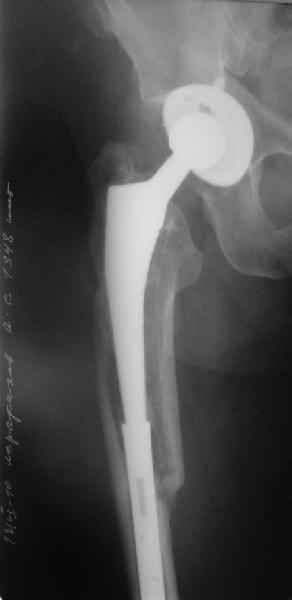

Re: Перипротезный перелом

Перелом бедра сросся. Конечность опорная и безболезненная, ходит без трости. Ножка, похоже, реинтегрировалась, как и надеялись. Снимки и фото в приложении. Комментарии приветствуются.

Надо ли что-то делать дальше, как полагаете? Убрать винты? Убрать "удлинитель ножки"? Или оставить все, как есть? Спасибо заранее.